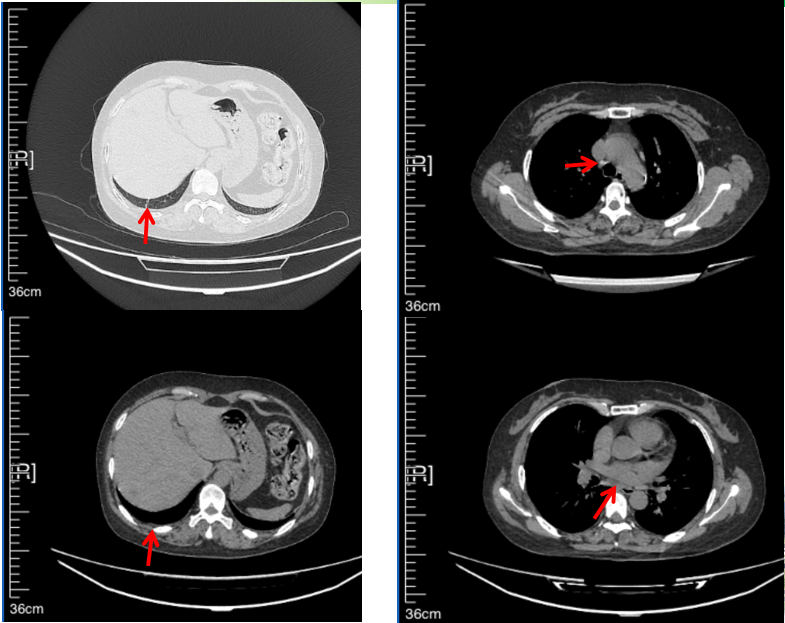

治疗经过:2023年3月27日始行恩沙替尼靶向治疗至今,最佳疗效为PR,末次评效为维持PR。期间出现轻度肝功能异常(DILI 1级),对症处理后好转。截止目前PFS为26个月。

2024年6月复查PR(最佳疗效)

2024年12月复查维持PR

2025年3月复查维持PR